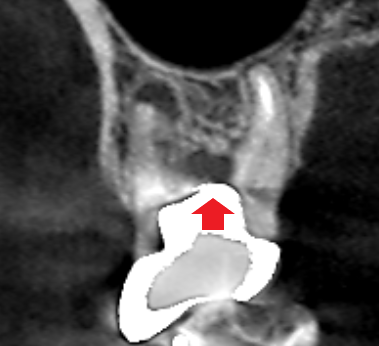

上顎第一大臼歯の初診時の冠状断のCT画像です。

赤い矢印の先の歯根の分岐部に黒い膿の影がみられます。土台が歯根の分岐部を貫通しているのが、膿の原因と考えられます。